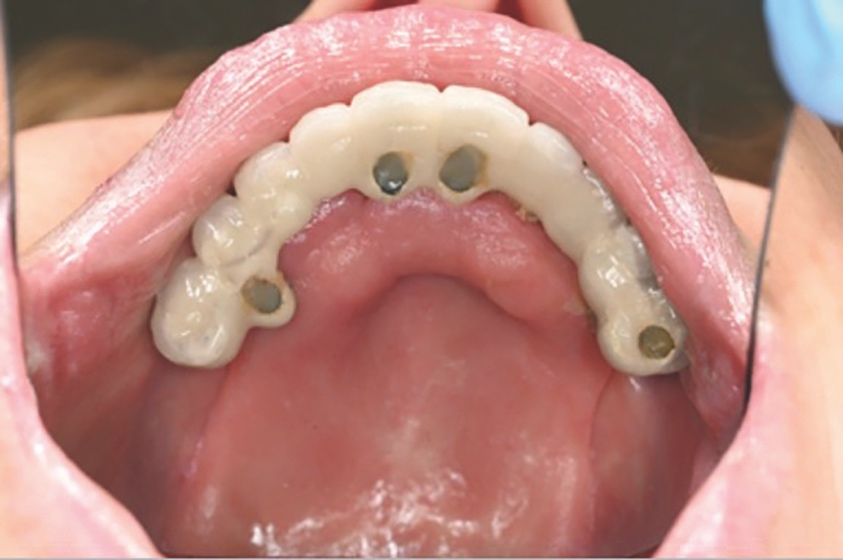

A follow-up orthopantomogram revealed that all implants were healing well (Figure 7). The shortened dental arch (SDA) concept was used to restore this patient’s occlusion, and a maxillary bridge and mandibular implant-retained denture were used to restore second premolar to second premolar in each arch (Figures 8 and 9). SDA was introduced in 198114 and is a problem-oriented method that aims to minimise complex restorative treatments.14 It outlines maintaining at least four posterior occlusal units or a minimum of 20 well-distributed teeth to ensure a functional, natural and healthy dentition.15

Careful digital restorative planning enabled a functional and aesthetically pleasing outcome to be achieved with a maxillary bridge and a mandibular implant-retained and -supported denture (Figures 12 and 13). Enhancements in the speed of osseo-integration, the strength of dental implants and the range of prosthodontic materials contributed to the restorative success.